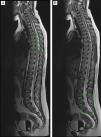

Dada la mala evolución, se solicita resonancia magnética (RM) con (fig. 1A) signos de meningitis infratentorial (fig. 1B), ventriculitis generalizada y encefalitis isquémica supratentorial. Tras mejoría clínica, se procede a la extubación a los 5 días y se objetiva paraparesia flácida arrefléxica con hipoestesia y síndrome de cola de caballo. La RM medular compatible con mielitis transversa1 (fig. 2A) y presencia de material purulento en fondo de saco dural con radiculitis2 y aracnoiditis de la cola de caballo (fig. 2B).

RM craneal secuencia T2 horizontal donde se aprecia: A) Alteración de señal en surcos a nivel supratentorial. B) Alteración de señal con restricción patológica de epéndimo ventricular de ambas astas occipitales y tercer ventrículo, mínimo del cuarto, así como algo de contenido purulento declive en ambas astas occipitales.